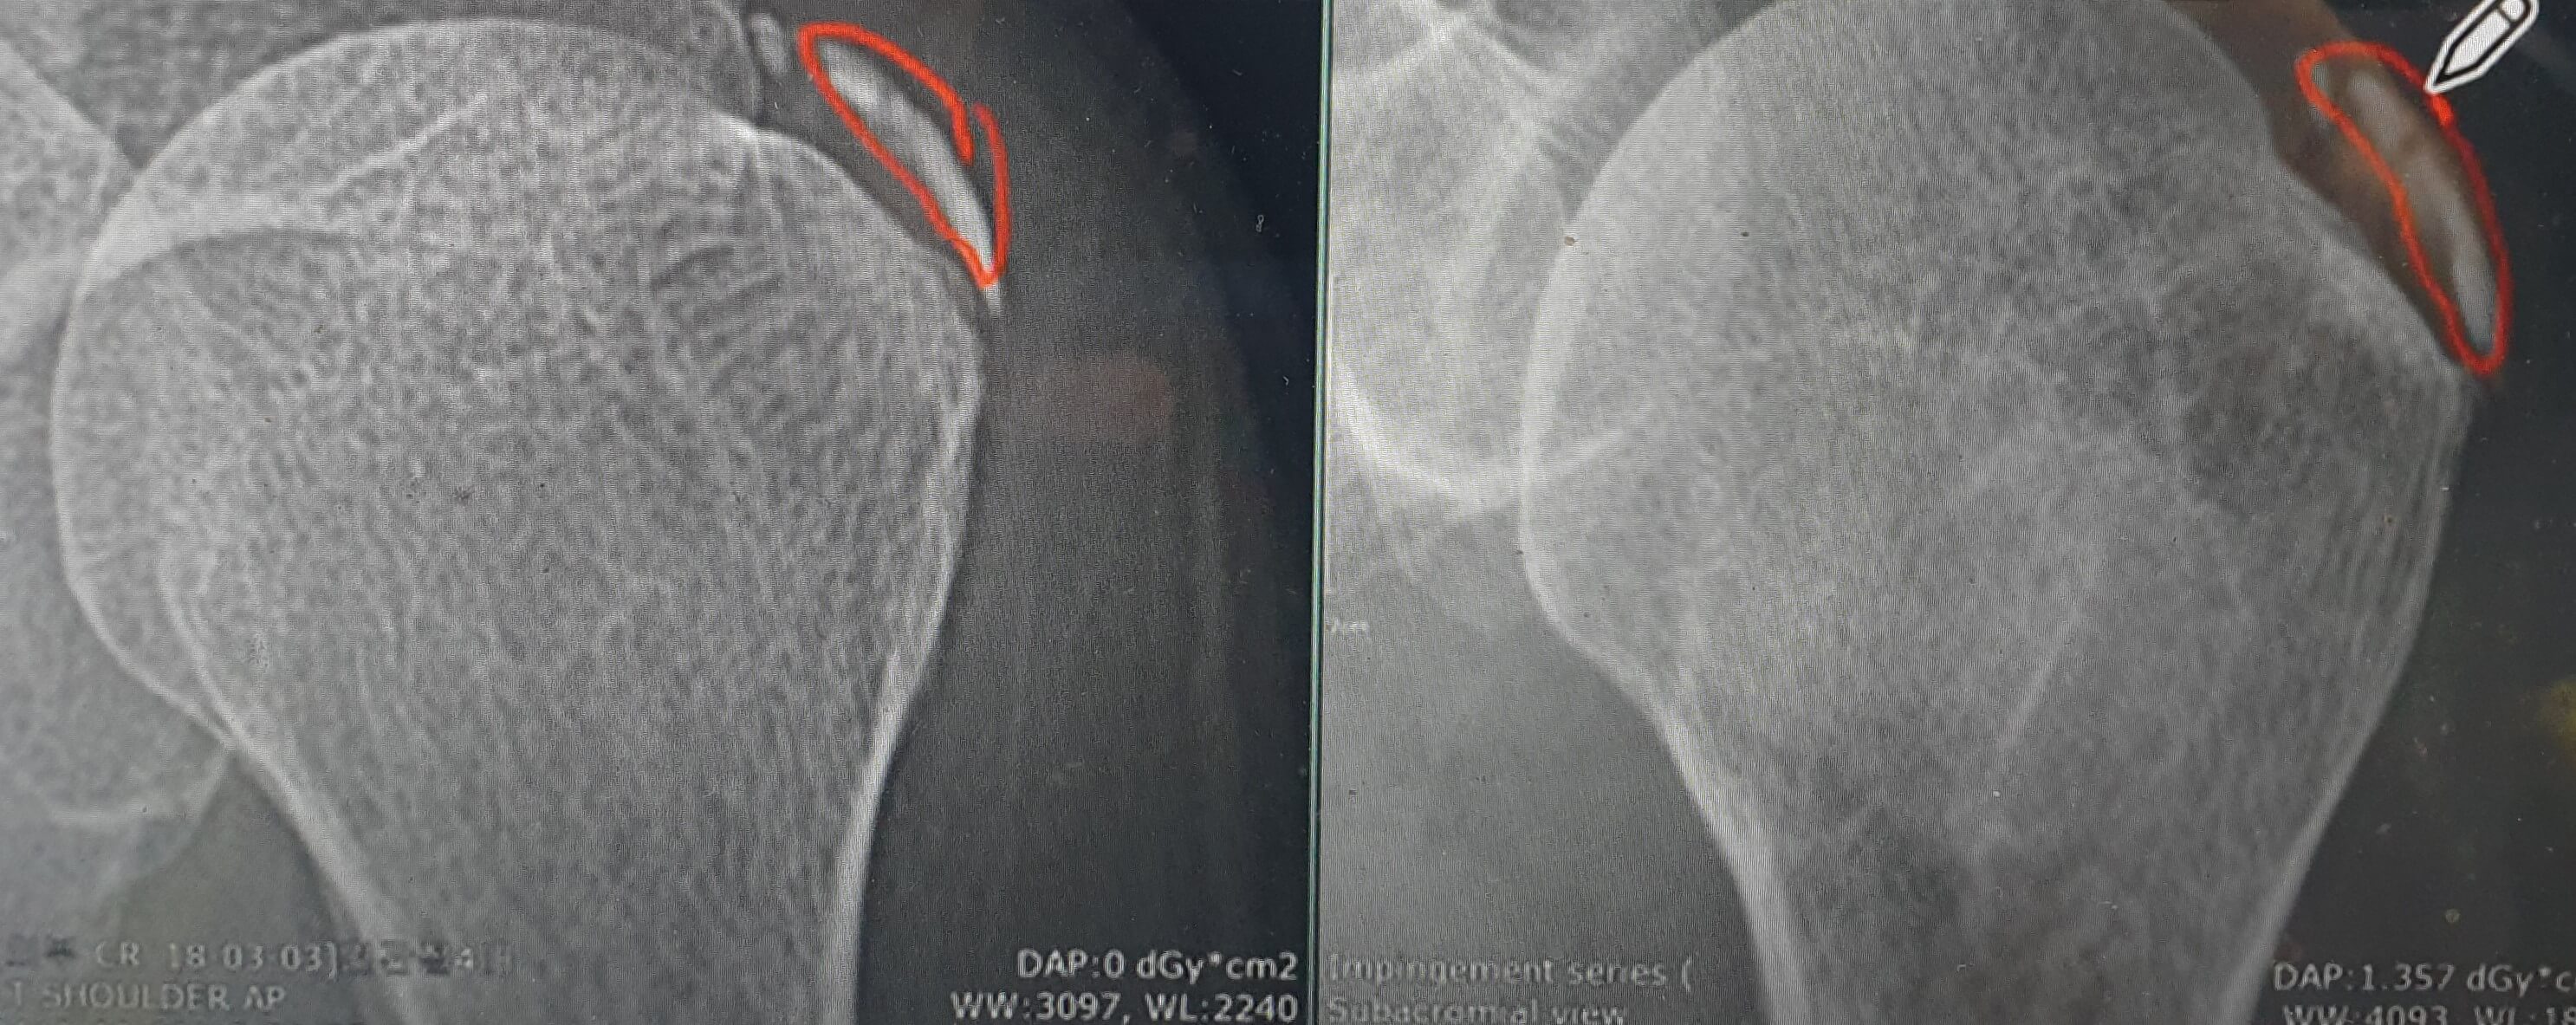

위 사진 속 화살표가 가리키는 것이 바로 석회결절이며 흡사 분필 같기도 합니다.

문제는 이 석회결절이 녹아내리면서 주변 조직 혹은 활액막에 아주 심한 염증을 일으켜 그 부분이 당기거나 눌리게 되면 심한 통증을 유발한다는 것입니다. 따라서 실제로는 석회결절 때문에 생기는 통증인데 이것이 회전근개 힘줄 손상이나 내측측부인대 문제 거나 TFCC(삼각섬유연골복합체)로 오해받는 경우가 상당히 많습니다.

처음에는 사진의 왼쪽처럼 딱딱했던 석회 결절이 점차 오른쪽 사진처럼 두리뭉실해지고 묽어지고 부풀어올라 더 커지는 양상을 보입니다. 석회가 녹아내는 것인데 석회가 녹아내릴 때 통증이 극심해지게 됩니다.